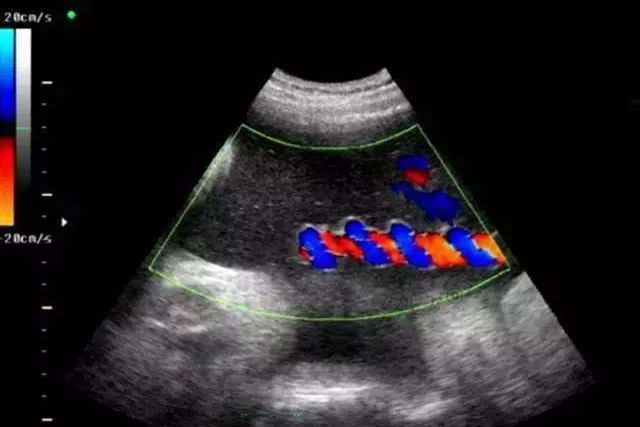

比如做个B超,但是要和医生强调检查脐带扭转这项。因为一般在做B超的时候,不会检查脐带是否扭转。

也可以通过胎心监护的方式,判断胎儿是否有脐带扭转情况,想要判断脐带是否过度扭转还可以通过下面几个方式进行判断:

- 脐动脉

孕妇在孕晚期时候,脐动脉血流S/D值如果超过3.0就表示脐带可能扭转了,因为正常情况下,随着妊娠的发展逐渐减低,在三十二周后脐动脉血流S/D值会小于3.0。